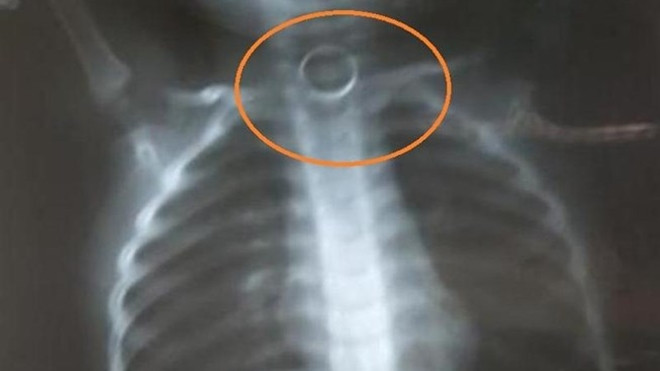

Qua chụp X quang, bác sĩ phát hiện vòng kim loại đường kính khoảng 2cm nằm ở thực quản ngang đốt sống cổ số 6-7 của bé. Để an toàn cho bệnh nhân, đồng thời do BV chưa đủ các kỹ thuật hỗ trợ như ống nội soi cho trẻ nhỏ, bác sĩ trực đề nghị chuyển bệnh nhân đi Hà Nội.